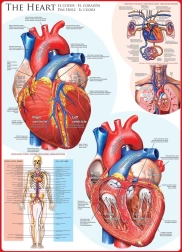

Dive into the world of jigsaws, where every piece clicks into a perfect picture. Puzzles offer creative relaxation, train memory, focus, and spatial imagination, and are ideal for time together with family. In this category you’ll find classic 500, 1000, 1500, and 2000+ piece puzzles, panoramic puzzles, jigsaws featuring landscapes, cities, animals, art, and movie themes including licensed series. Thanks to precise die-cutting, a matte, anti-glare finish, and high-quality print, the pieces fit beautifully and the final image stands out with vibrant colors.